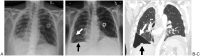

Infectious, traumatic, or neoplastic processes in the chest often result in fluid collections within the pleural, parenchymal, or mediastinal spaces. The same fundamental principles that guide drainages of the abdomen can be applied to the chest. This review discusses various pathologic conditions of the thorax that can result in the abnormal accumulation of fluid or air, and their management using image-guided methods.